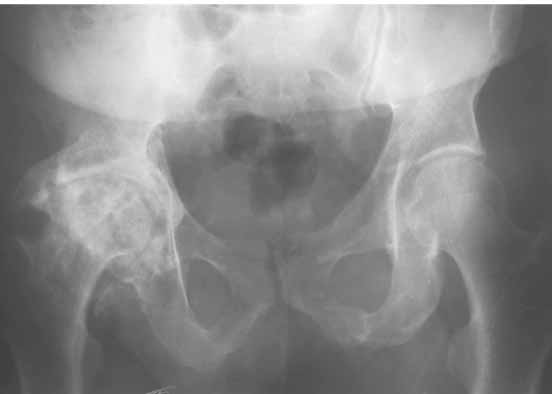

Для ответа на Ваши вопросы нужна, как минимум, обзорная

рентгенограмма таза в прямой проекции - многое станет ясно без слов.

GG> Для ответа на Ваши вопросы нужна, как минимум, обзорная

GG> рентгенограмма таза в прямой проекции - многое станет ясно без слов.

Правильно ли я понял,что нужна рентгенограмма всего таза?

Если надо - сделаем.

Уважаемый Александр Александрович,

Обзорная рентгенограмма таза просто необходима. Удивительно, почему она не сделана сразу же после установки протеза.

После ее получения можно будет продемонстрировать причины проблемы.

> Обзорная рентгенограмма таза просто необходима. Удивительно, почему

> она не сделана сразу же после установки протеза.

> После ее получения можно будет продемонстрировать причины проблемы.

Да, это разумно.

Причем рентгенография должна быть сделана с правильной укладкой пациента, а именно - голени должны свешиваться с рентгеновского стола и край стола проходить на уровне коленных суставов.

Тогда можно будет точно установить угол антеверсии.

1. AP X ray of the Pelvis is a must. It will likely show that right hip/ femur is longer than left. Even based on Rt Hip AP X Ray it is my impression.